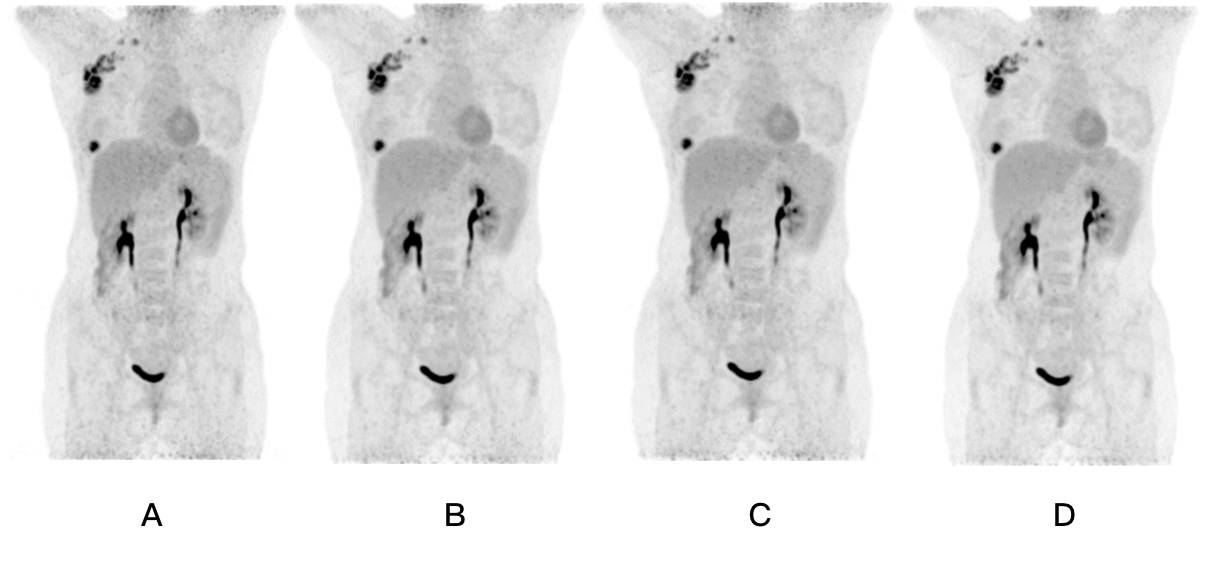

一般常理认为,同等条件下,PET-CT扫描时间越长,获得病灶定量测量信息越多,图像噪声越小,从而提升诊断精度。而在SNMMI大会上,联影与南京市第一医院共同发布了一项另辟蹊径的科研成果。目前,联影112环数字光导PET-CT凭借业界最高灵敏度与轴向视野,可将过去传统设备长达近20分钟的全身扫描缩短至6分钟!但以此为基础,是否还有可能将扫描时间减半?!联影与南京市第一医院合作,根据大量临床实验案例进行数据分析,结果表明,在同等条件下,基于联影112环数字光导PET-CT的3分钟 全身扫描与6分钟全身扫描图像相比,病灶(如肿瘤)的定量测量信息差别并不显著,且图像噪声均处于可接受范围内。换言 之, 同等条件下,PET-CT扫描时间的缩短对病灶的定量测量信息影响不显著,可满足医生诊断需求!这一学术成果为联影进一步研究针对某些特定疾病的快速、超低剂量扫描提供了可能的方向。

图A到图D分别为扫描时间为3分钟、4分钟、5分钟和6分钟情况下的全身成像。可以看到病灶的定量测量信息几乎没有差别,且图像噪声处于可接受范围内。